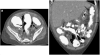

Results: The most common presenting symptoms were abdominal pain, bloody diarrhea and rectal bleeding. EC was characterized as a dense and predominantly eosinophilic inflammatory infiltrate in the lamina propria or epithelium without granulomas. CT scans were abnormal in six children (86%), demonstrating colonic wall thickening, predominantly cecal, in five (71%), mild to moderate terminal ileal thickening in two (29%), and pneumatosis in one (14%). Right colonic involvement was greater than terminal ileal involvement.

Conclusion: CT imaging findings in children with EC include right colonic wall thickening of variable extent downstream and absent or mild involvement of the terminal ileum. EC should be considered in the differential diagnosis in children presenting with abdominal pain and bloody diarrhea.